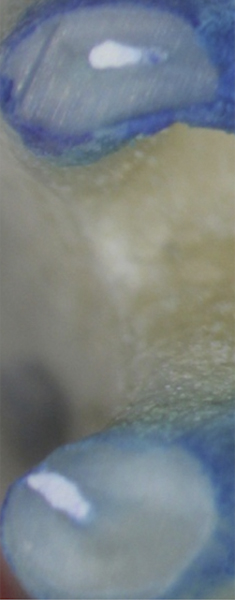

Fig 1. through Fig 3. Root filled with bioceramic sealer cut at different distances from the apex (Fig 1 through Fig 3: 0.5, 1.5, and 3.0 mm). One gutta-percha point is used as a plugger to move the sealer using hydraulic pressure. Note the irregularities are very well filled.

Figure 1

Figure 2

Figure 3

Pre-mixed BC Sealer is the only pure medical-grade bioceramic product available as a sealer for endodontic obturation. It has the same basic chemical composition as the other pre-mixed bioceramic products, but it is less viscous, which makes its consistency ideal for sealing root canals. It is used with a gutta-percha point, which is impregnated on the surface with a nano particle layer of bioceramic. The gutta-percha is used primarily as the delivery device (plugger) (Figure 1 through Figure 3) to allow hydraulic movement of the sealer into the irregularities of the root canal and accessory canals (Figure 4 and Figure 5).